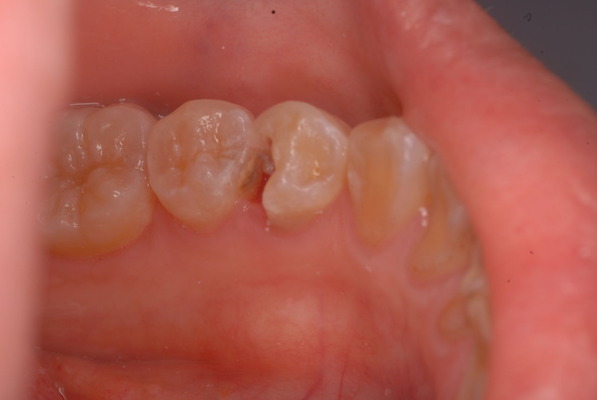

歯が痛くていつも通っている歯科で見てもらったところ虫歯が酷く、

注射もせずに取れるだけ虫歯という病原菌を丁寧に除去し、消毒し、ぎりぎりのところで鎮静効果を持つセメントで被覆するのです。

まだ虫歯は残っていますが危険なので除去せずにそのまま消毒して鎮静セメントを挿入しました。

隣の歯との間をプラスチックで閉鎖し、唾液の侵入を防ぎました。でもまだ虫歯は残っています。